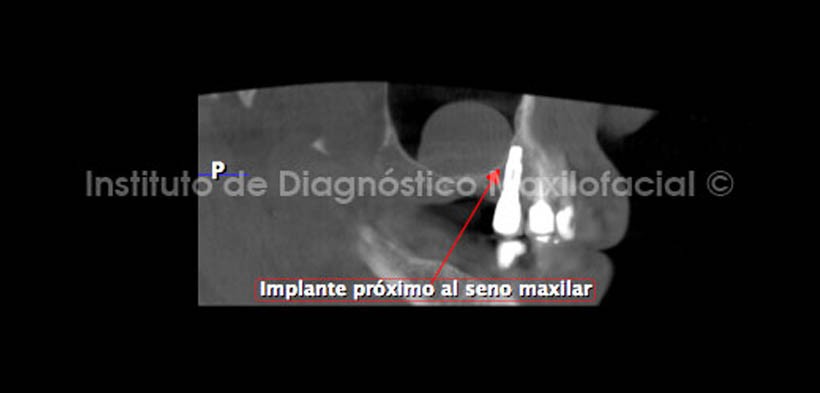

Por otro lado, se observa la estrecha relación del implante correspondiente a la región de la pieza 15 con la pared medial del seno maxilar (Fig. 7).